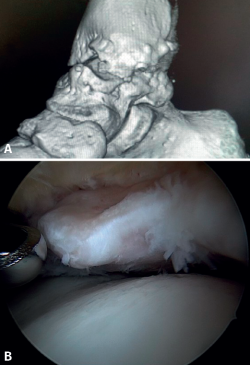

El PAT óseo por osteofitos también ha sido relacionado con la presencia de inestabilidad crónica. Se ha postulado que la alteración en la cinemática articular secundaria a la insuficiencia ligamentosa favorece el desarrollo de osteofitos en la región anterior de la tibia y el astrágalo(36,37). Estudios recientes han cuestionado la teoría de tracción capsular repetida como origen de los osteofitos en la práctica deportiva(38), ya que es fácilmente demostrable que los osteofitos se localizan intraarticulares por dentro de la inserción capsular, en el contexto de una artroscopia de tobillo (Figura 2). Por ello, la artroscopia con dorsiflexión de tobillo es fundamental para poder resecar los osteofitos de forma segura sin daño capsular ni a las estructuras suprayacentes, mientras que la técnica clásica de tracción (invasiva o no) dificultaría enormemente su resección, por lo que hoy en día se desaconseja su uso rutinario(3,39). Vega distingue dos tipos de osteofitos(3), según sean por trauma repetitivo (forma de pico) o por inestabilidad (en forma de visera). El concepto de microinestabilidad se asocia a microtraumatismos de repetición que podrían ser el origen de osteofitos con esta morfología característica (Figura 3).

Figura 2. Osteofito anterior de la tibia. A: en dorsiflexión la cápsula se separa del osteofito permitiendo su resección (B) mediante fresado.

Figura 3. Osteofito por inestabilidad crónica. A: el osteofito conforma un tope óseo que se extiende en el borde anterior del plafón tibial y la cara anterior del maléolo medial; B: imagen artroscópica.

La resección de osteofitos se realiza deslizándose desde su parte superior, rebajando gradualmente hasta alcanzar la zona articular (Figura 2). Con una pinza de tipo basket se puede resecar la zona más cercana a la articulación (Figura 5). Suele ser útil intercambiar los portales de visión y trabajo para visualizar y resecar completamente los osteofitos. Para el pinzamiento de partes blandas, un sinoviotomo de 3,8 o 4 mm suele ser suficiente. El vaporizador es útil en pinzamientos compactos, típicos de condiciones postraumáticas o reintervenciones, también para delimitar la parte ósea del osteofito antes de su resección.